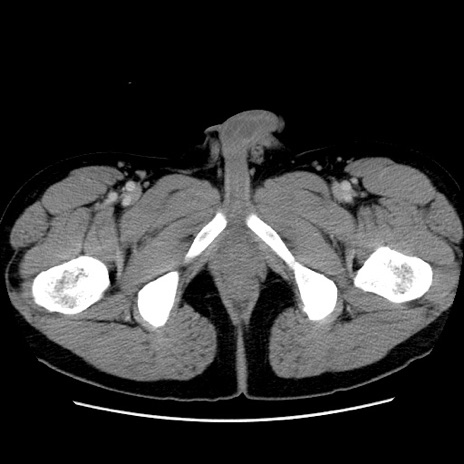

症例4(横断像)

【症例】30歳代男性

【主訴】腹痛、嘔吐

【現病歴】昨晩から突然の腹痛あり、その後嘔吐、軟便も出現。腹痛が改善しないため救急搬送となる。2日前にしめ鯖の食事歴あり。

【身体所見】意識清明、苦悶様、BP 135/90mmHg、BT 35.7℃、腹部:平坦、やや硬、心窩部〜臍部に自発痛、圧痛あり、筋性防御+、反跳痛-

【データ】WBC 8100、CRP 0.57